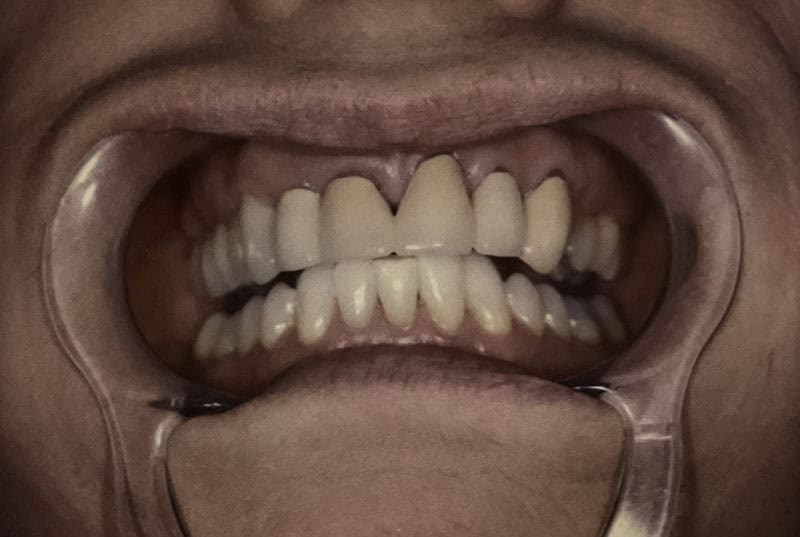

Before

After

Custom Dental Veneers

Case Highlight